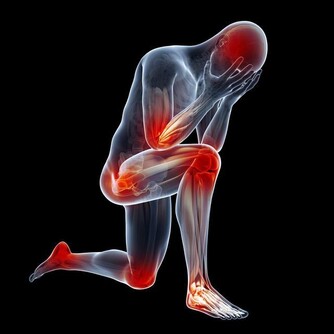

血管年輕了,身體的疾病也就少了,獲得也就更健康了。血液一旦變得粘稠,就會導致血栓、心肌梗死等等疾病,現在很多二三十歲的年輕人已經擁有三四十歲的血管,只是他們還不自知,一起來看看怎麼判斷血管是否還好嗎。

3、堅持鍛煉定期體檢